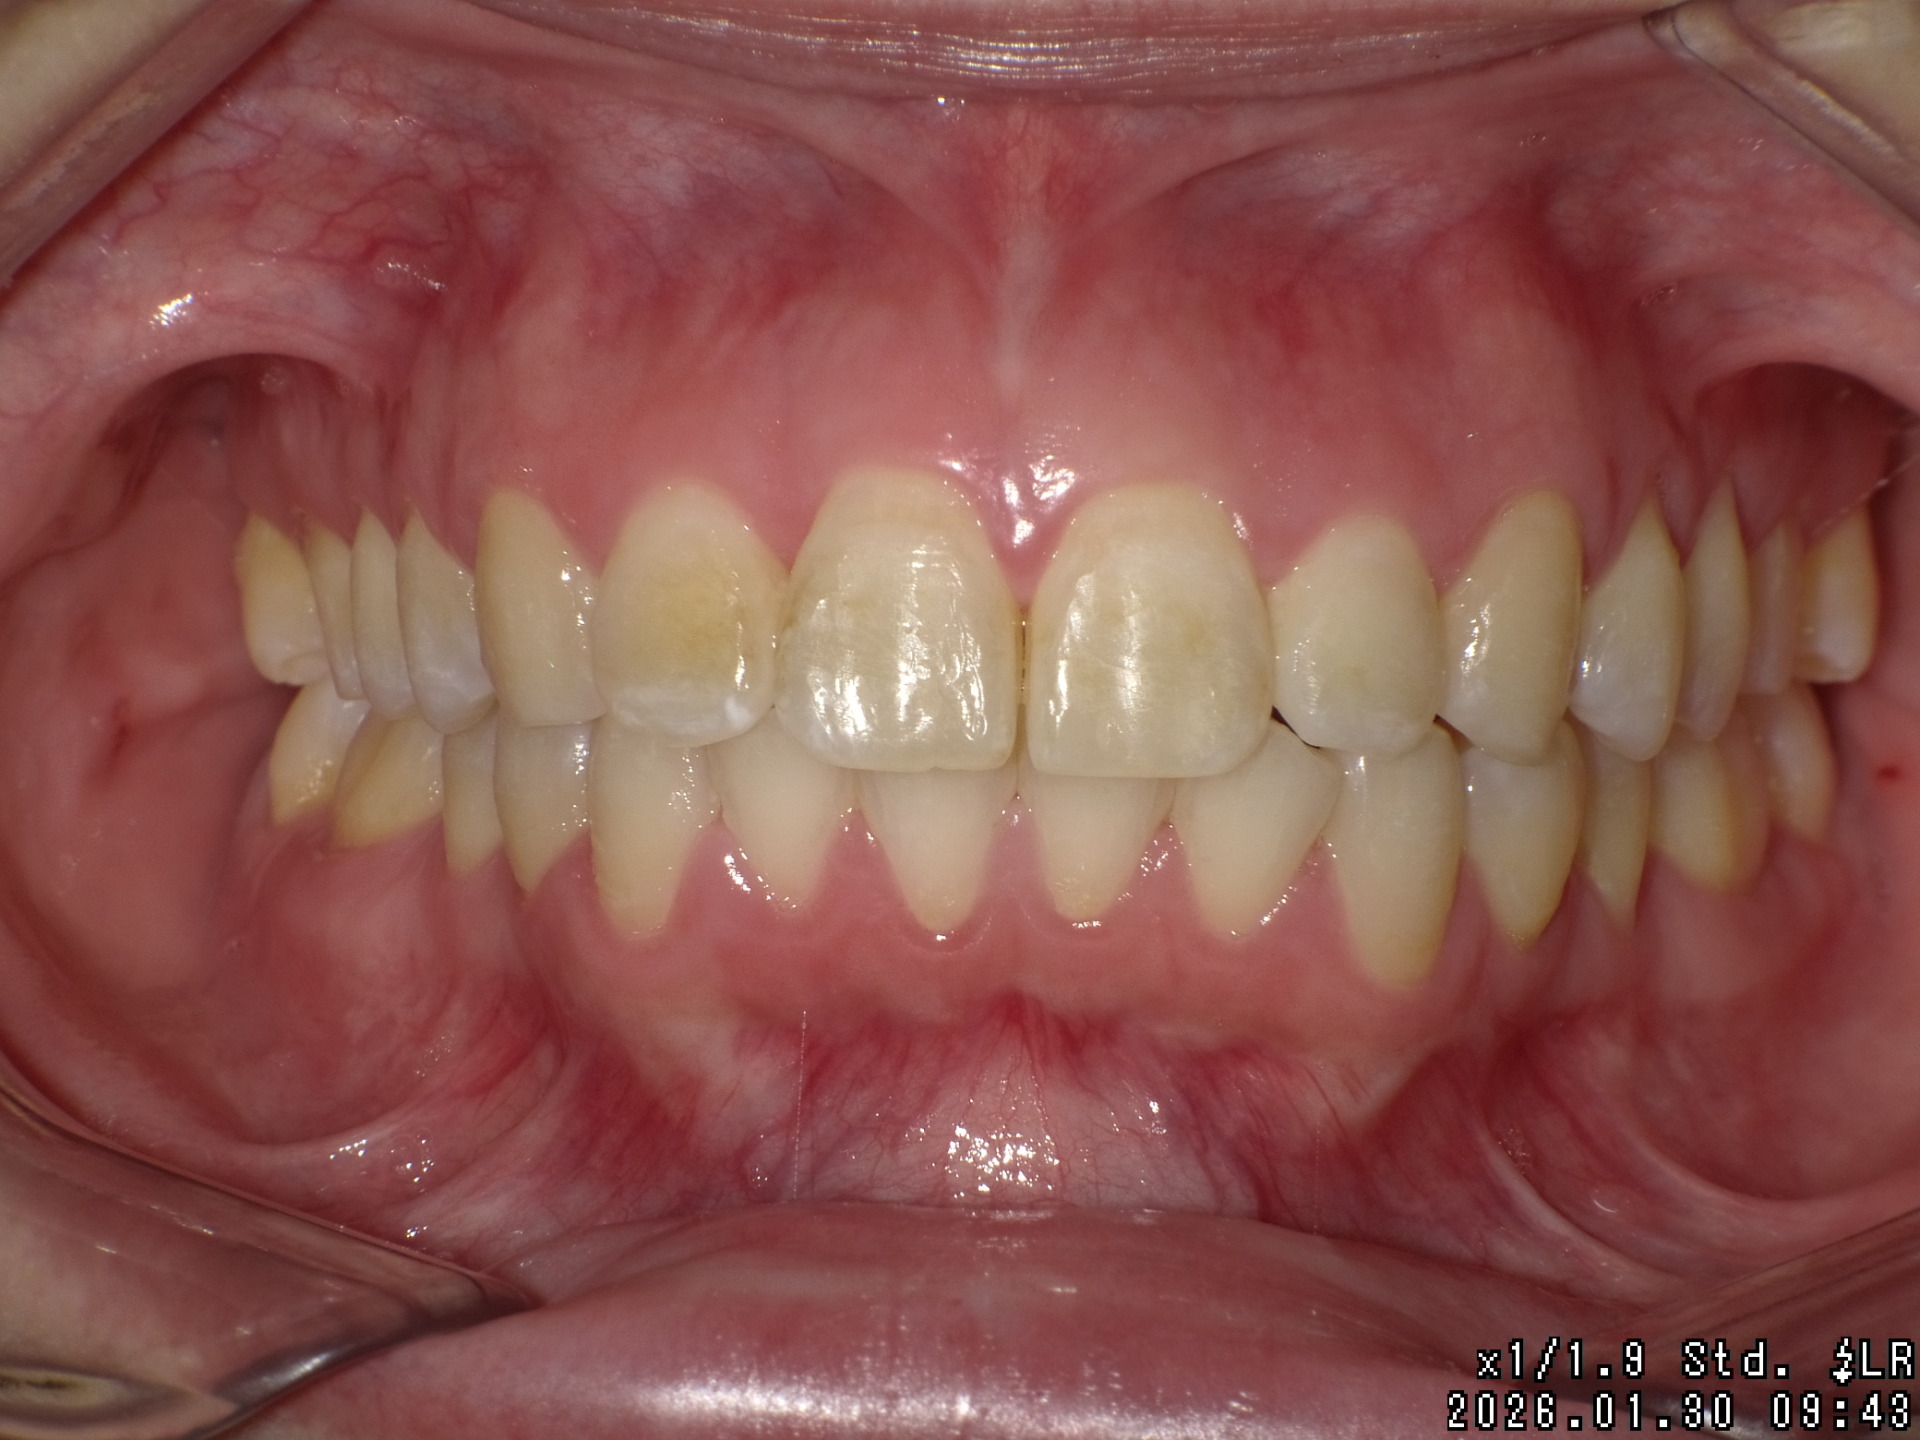

Before

| 症状 | 前歯が出ている |

| 通院目的 | 永久歯を抜かずに歯並びを治したい。 |

| 処置内容 | ディスタライザー・マルチブラケット装置 |

| デメリット・院長コメント | 永久歯を抜かない治療のデメリットは、治療期間が長いことです。 ただし、その後の人生の長さを考えると、健全な小臼歯を2本または4本抜歯の矯正治療よりも、はるかにメリットがあるといえます。 また、アーチが小さくならないので、舌が後ろに押し込まれないためいびき防止につながり睡眠の質の向上にもつながります。 |